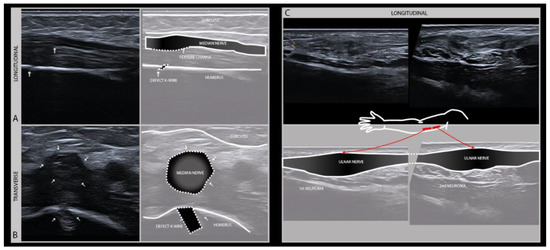

The therapeutic window for nerve surgery depends on an accurate assessment of the extent of the damage, which can usually be done clinically and may be augmented by EMG, localizing the exact site of the lesion and hence the distance between the lesion site and the affected muscle and skin, and detecting morphologic alterations of the damaged nerve that indicated transection or intraneural scarring (Figure 5). This information will guide surgical decision making by assessing the regenerative potential [25].

Figure 5.

Longitudinal (A) and transverse (B) images of the left median nerve in the distal upper arm of a 5-year-old boy with a supracondylar humerus fracture surgically treated with K-wire fixation. The subsequent median nerve lesion with a change of nerve architecture seen near the bone defect after K-wire removal (high frequency probe 19–24 MHz). Full recovery within weeks after K-wire removal. Longitudinal (C) images of the ulnar nerve in the upper arm with two serial neuromas after a local gunshot wound.

A particular feature of traction injuries, that one has to be aware of, is the mechanical effect that can occur on more distal parts of the nerve, away from the site where it was primarily damaged. The most vulnerable distal nerve regions are the points where the nerve is anatomically anchored to its surroundings, such as at the level of a bifurcation, or beneath or between a strong fascial structure. So, in sciatic nerve trauma one has to actively look for a second lesion in the common peroneal nerve at the level of the fibular head, that might improve with surgical decompression. A similar phenomenon can be observed in axillary plexus trauma with the secondary affection of the musculocutaneous nerve where it bifurcates between the biceps and brachialis muscle, and with the trauma of the radial nerve that can show secondary changes to the posterior interosseus nerve at the level where it enters the supinator muscle; although the latter does usually not need specific treatment.